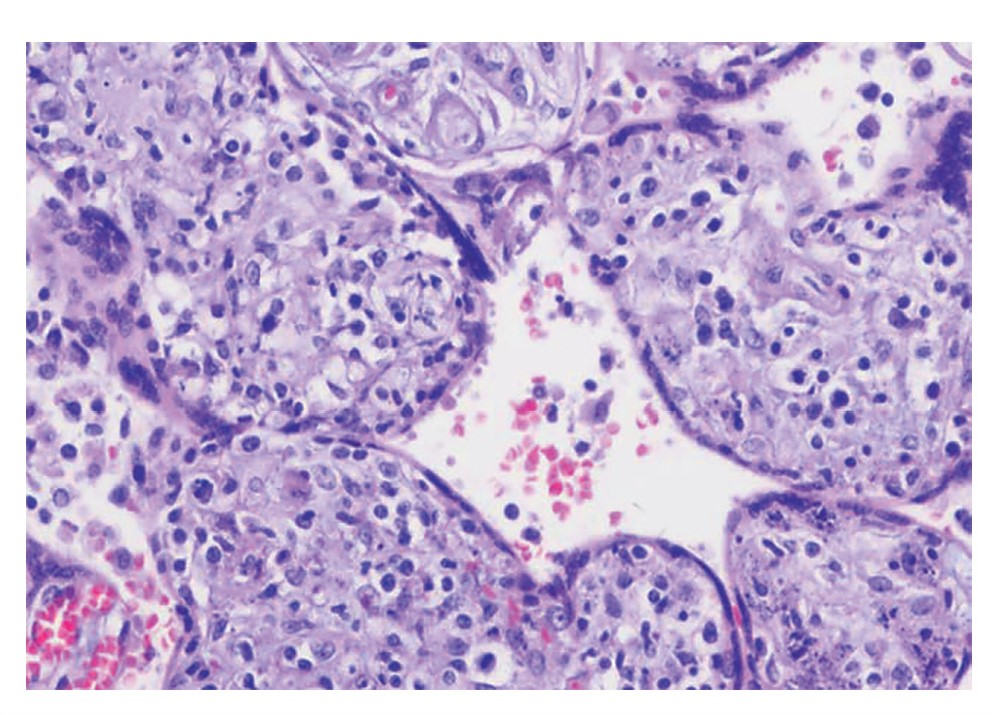

В большинстве наблюдений отмечены различные сочетания приведенных УЗИ-признаков (рис. 1–3).

Рис. 1. Эхограмма. ВУИ. Краевое прикрепление пуповины в режиме цветного допплеровского картирования.

Fig. 1. Sonogram. Intrauterine infection (IUI). Edge attachment of the umbilical cord in the color Doppler mapping mode.